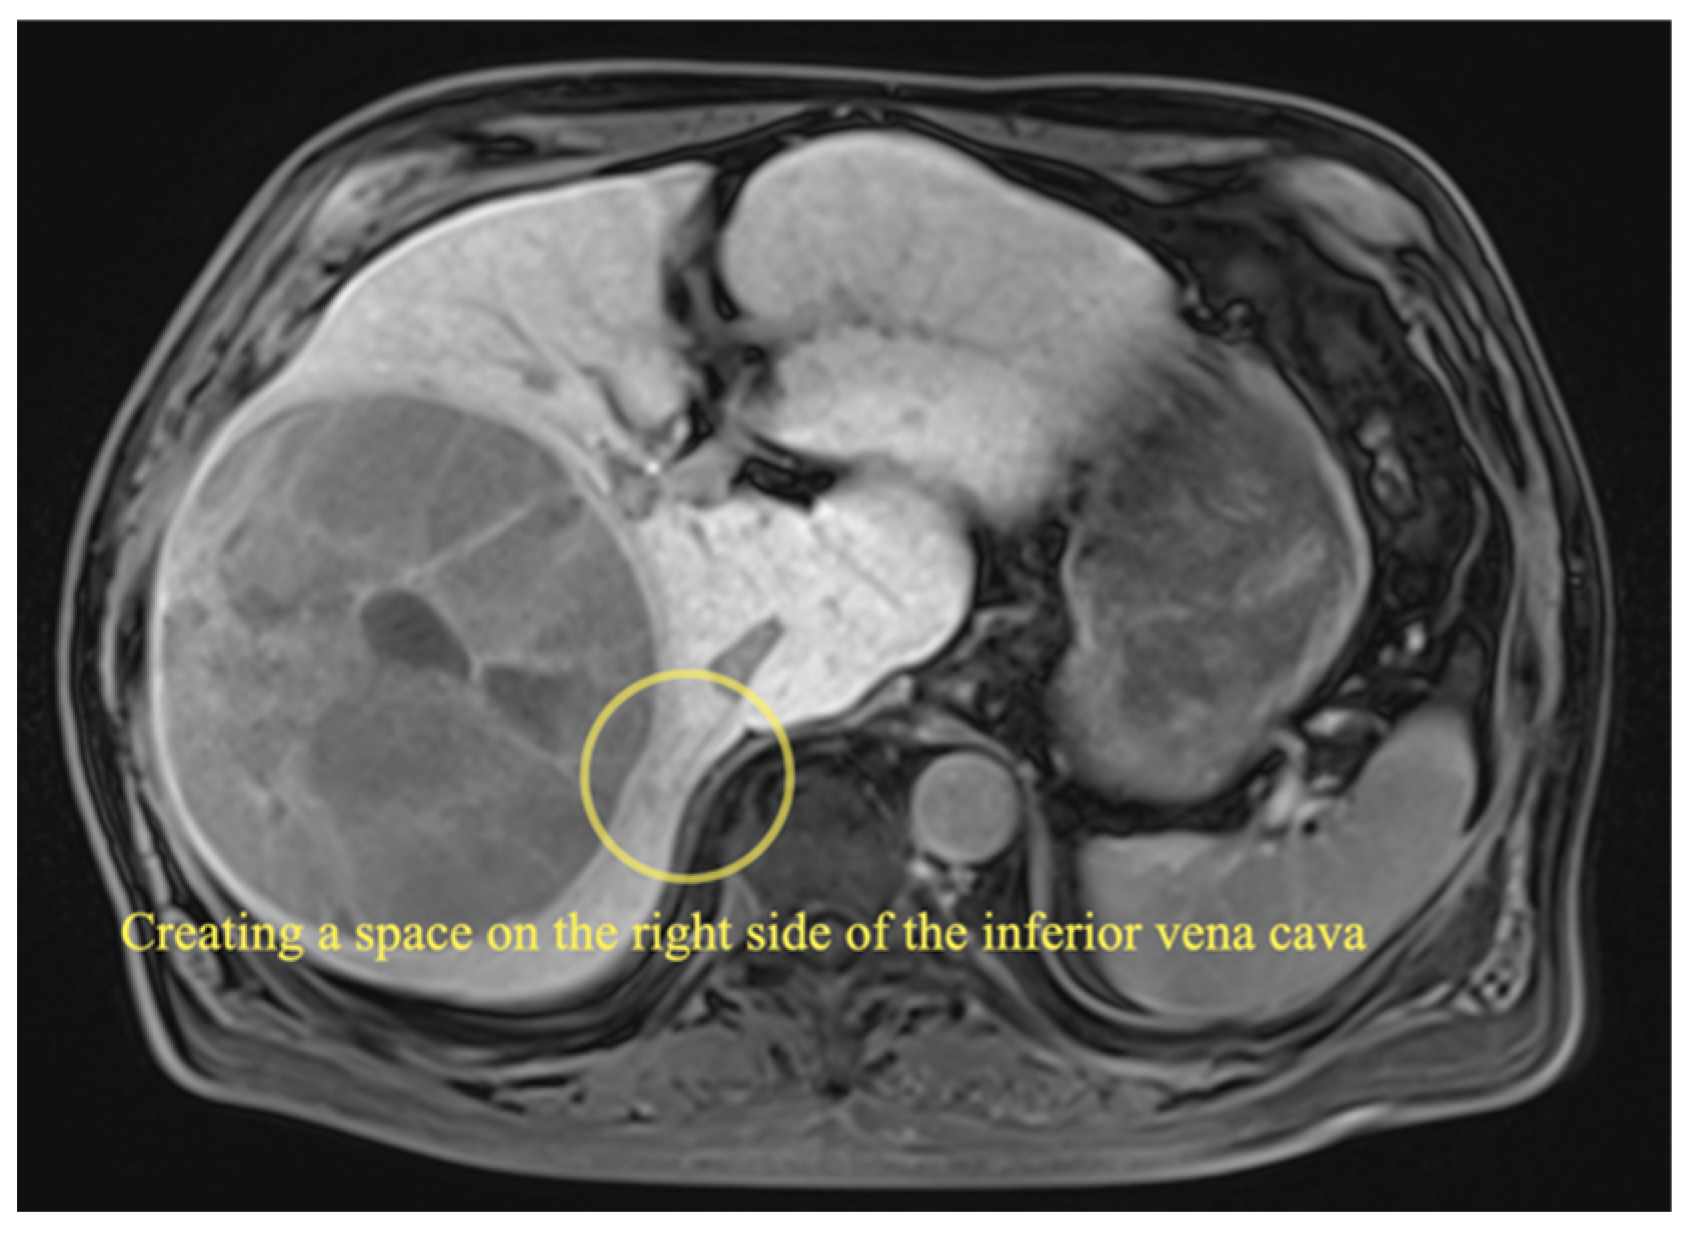

2.3.1. Right Hemihepatectomy